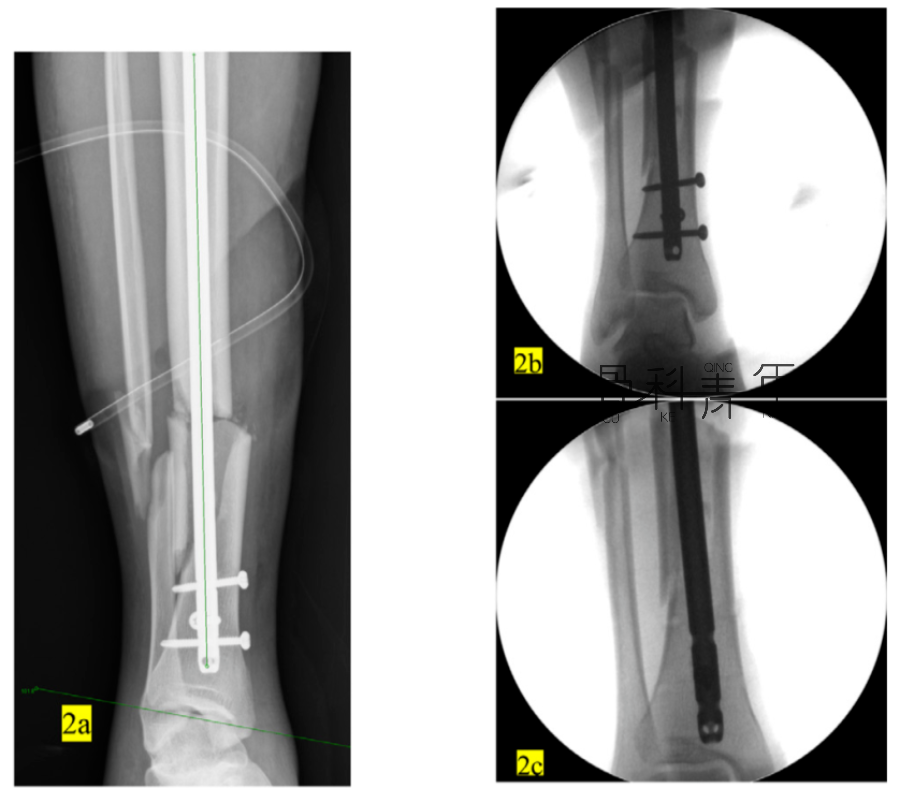

例2:

2a-2c:胫腓骨远端骨折,髓内钉固定,主钉插入及远端锁钉锁定后,可见骨折对线不良,存在移位。

2d-2f:依同法在移位平面拧入螺钉纠正移位,恢复对线后置入阻挡钉维持复位。